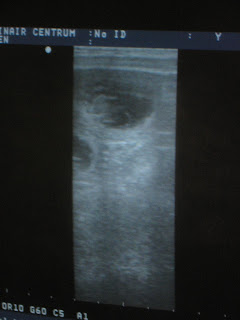

Maar de rit was echt niet voor niks geweest, want nadat de scanner op haar buikje gezet werd, zagen we meteen een gevuld vruchtblaasje op het scherm, en nog een, nog een en uiteindelijk zijn we gestopt met tellen bij 5 stuks.

Hieronder een aantal foto's die ik met mijn eigen camera heb gemaakt, want de printer van de praktijk wilde even niet meewerken...